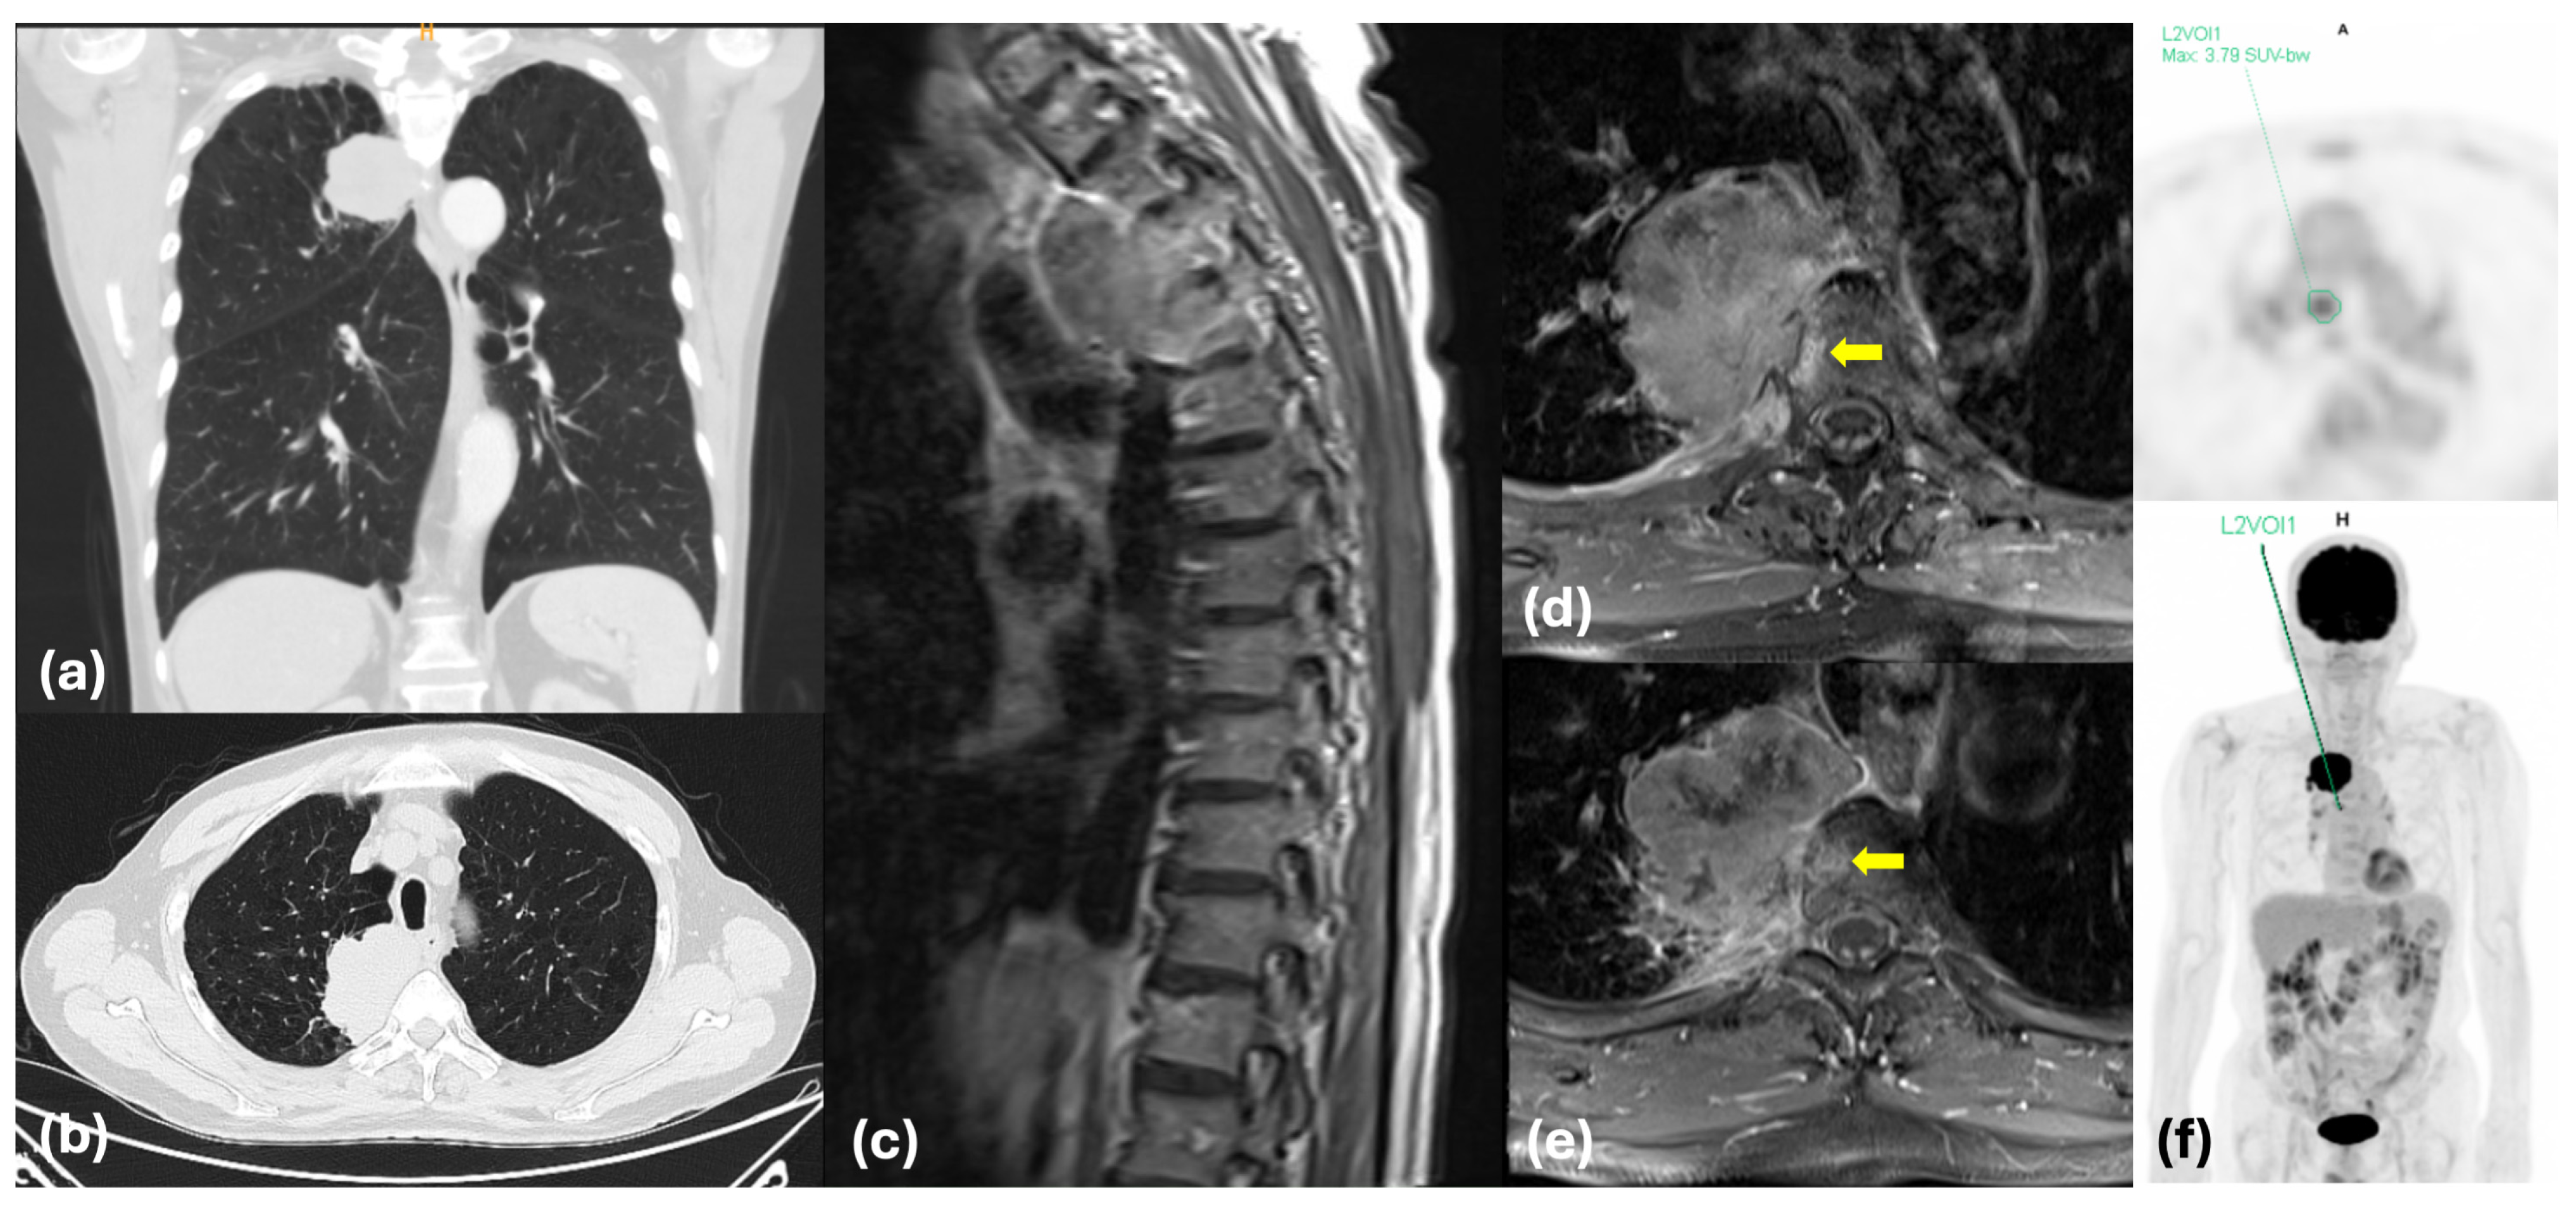

2.1. Clinical History

3.3. Diagnostic Advancements and Preoperative Hemostatic Optimization